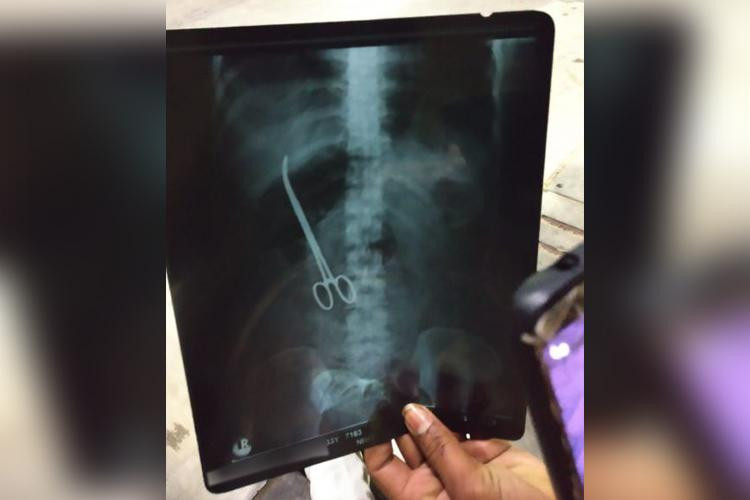

| Một cụ già đã gặp sự cố "hy hữu" với của quý của mình ở ngay trong bệnh viện (Ảnh: CNN) |